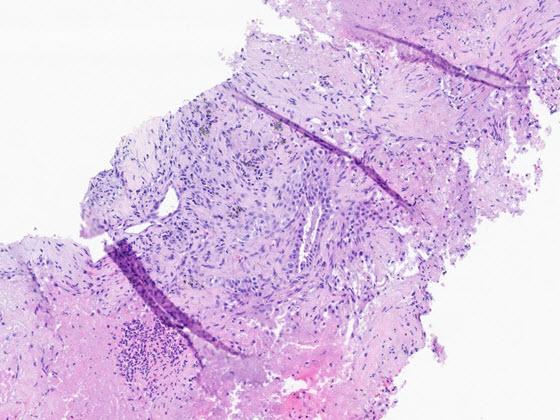

H&E slides depicting four types of digital pathology artifacts

Artifacts in Digital Pathology

High quality slides are a prerequisite for a first-rate digital workflow. Artifacts generated in the slide creation and scanning process can not only affect interpretation but can prevent image analysis and AI tools from rendering the correct results. SlideQC BF automatically detects and annotates artifacts present on images, increasing the accuracy and quality of the analysis results while maximizing scanned tissue. Artifacts may include pen marks, out of focus areas, tissue folds, debris, or bubbles.